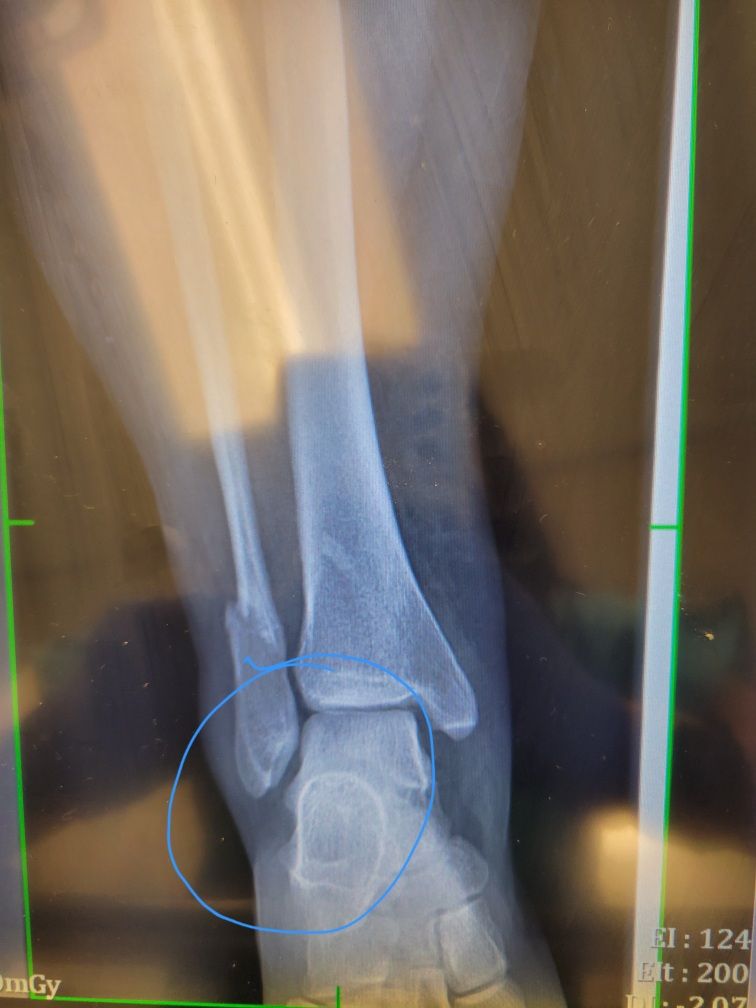

The Xrays showed two fractures, which would require surgery. BUT, I was in another state. I had to fly home, with crutches and a hard cast. Which required a full body pat down, wheelchair assistance and a whole mess of other fun things.

So, now we are 3 months and 6 days out from the accident. I am now officially walking without cane, boot or other assistance! 10 screws and 2 plates have been added to my ankle, essentially adding another reason for the aready paranoid airport people to pat me down each time I walk through the metal detector in airport security.